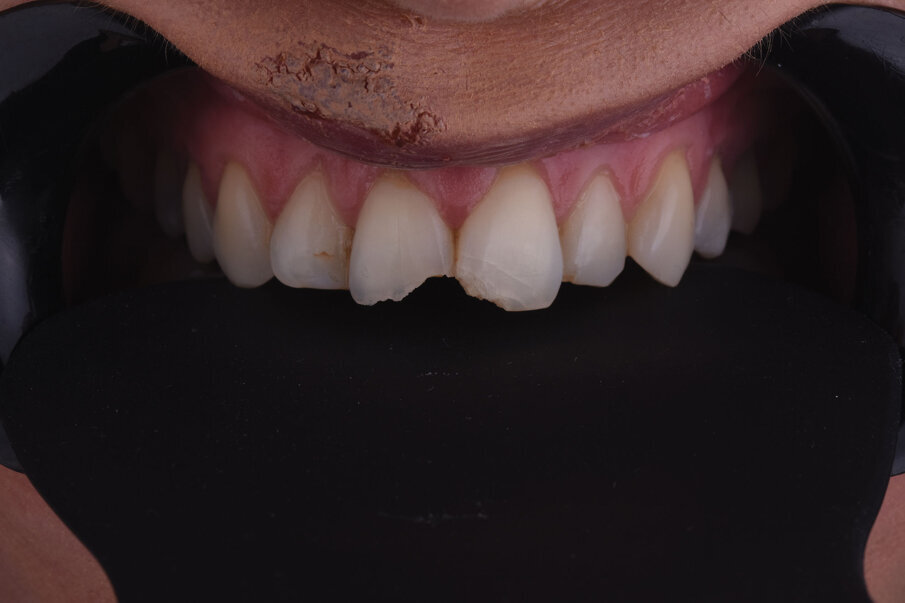

Sl. 2: Pozicija frakturiranih zuba u maksimalnoj interkuspaciji

Sl. 3: Palatinalni prikaz frakturne linije